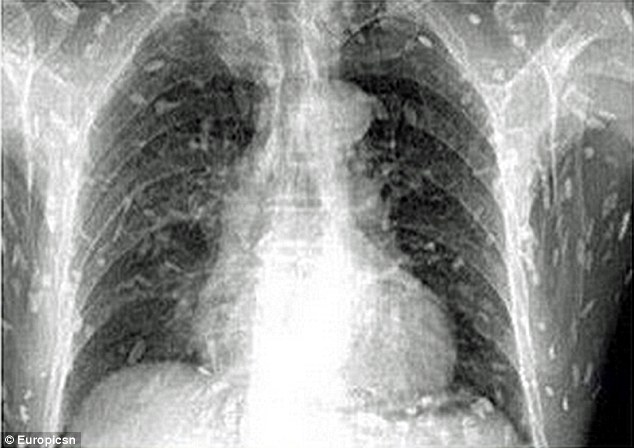

VBF-Một người đàn ông đã bị nhiễm sán nặng sau khi ăn quá nhiều món cá sống và phải đi cấp cứu. Mong mọi người hãy cảnh giác khi ăn các món cá kiểu này kẻo lại giống như trường hợp nầy.Sau khi ăn quá nhiều sashimi, một người đàn ông Trung Quốc đã phải nhập viện với biểu hiện ngứa da và đau dạ dày.

Kết quả chụp X-quang khiến anh chàng kinh hoàng thấy toàn bộ cơ thể mình bị nhiễm sán dây sau khi ăn quá nhiều sashimi – món cá sống cắt lát.

Các bác sĩ cho rằng, một số món ăn từ Nhật Bản chưa được nấu chín kỹ như thịt sống hoặc cá đều bị nhiễm ký sinh trùng. Người đàn ông này sau đó đã được điều trị tại Bệnh viện nhân dân số 8 Quảng Châu, ở tỉnh Quảng Đông, miền Đông Trung Quốc.Một số nghiên cứu đã chỉ ra rằng, ăn cá sống hoặc chưa nấu chín có thể dẫn đến xuất hiện một loạt các ký sinh trùng. Nhiễm sán dây xảy ra sau khi ăn phải ấu trùng diphyllobothrium, được tìm thấy trong các loại cá nước ngọt như cá hồi, mặc dù cá đã được ướp và hun khói, vẫn có thể truyền nhiễm loại sán này.

Tuy nhiên, bác sĩ Yin, ở bệnh viên Nhân dân Quảng Châu số 8 nói trên trang web smags.com rằng ăn thức ăn chưa nấu chín kỹ sẽ nhiễm trứng sán dây, khi giun trưởng thành đi vào dòng máu của con người, có thể gây ra bệnh giun sán. Đây là loại nhiễm trùng có thể gây tử vong khi giun sán phát triển lên đến não.